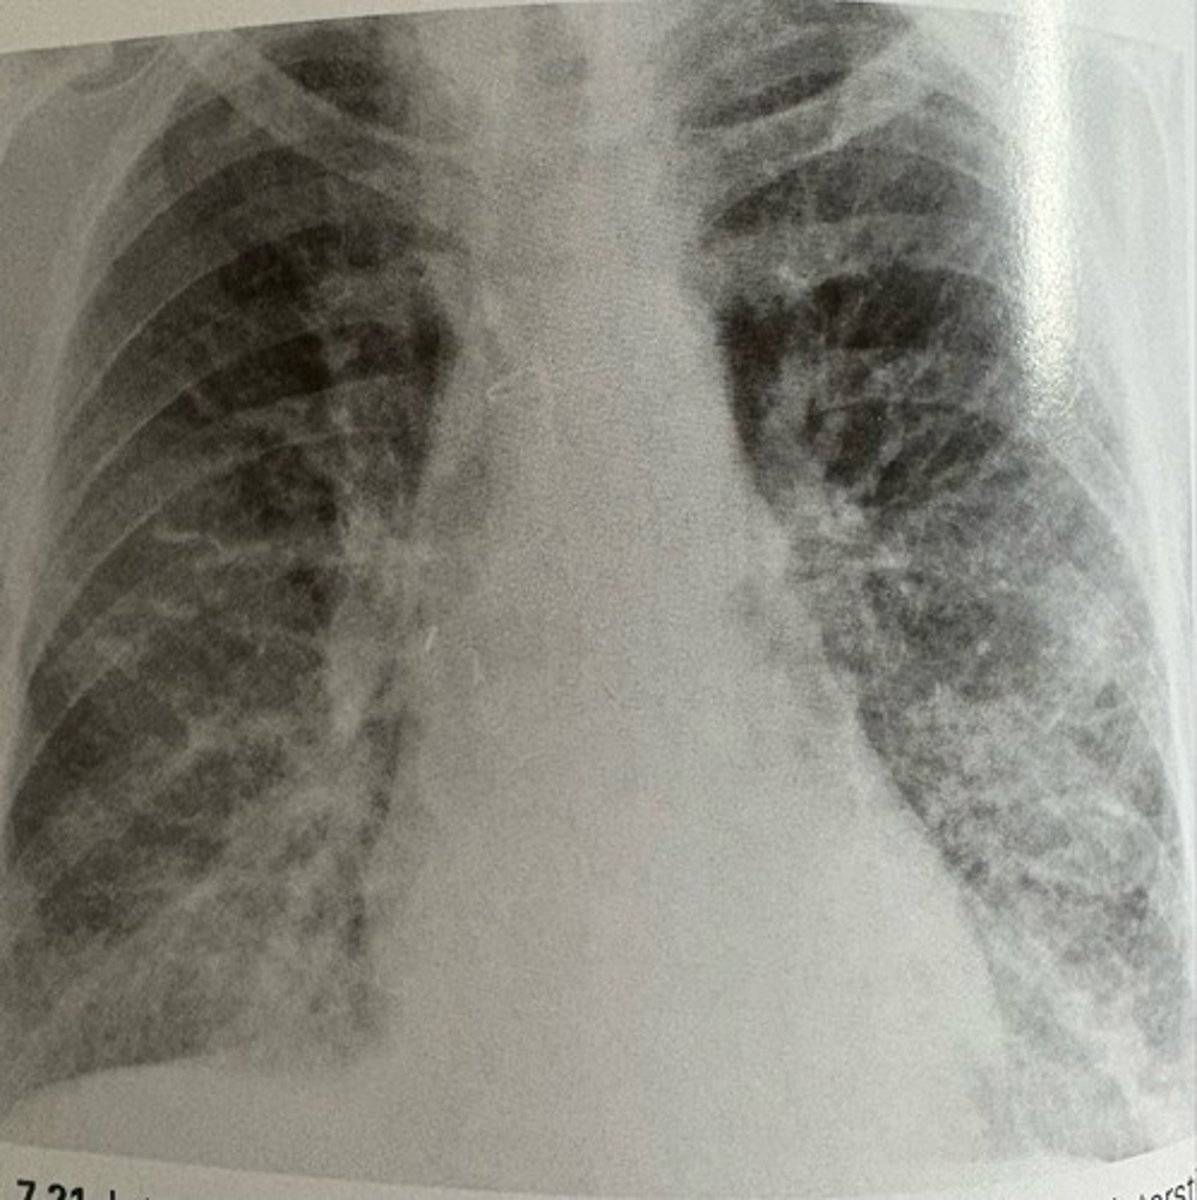

interstitial pulmonary edema

what pathology is present?